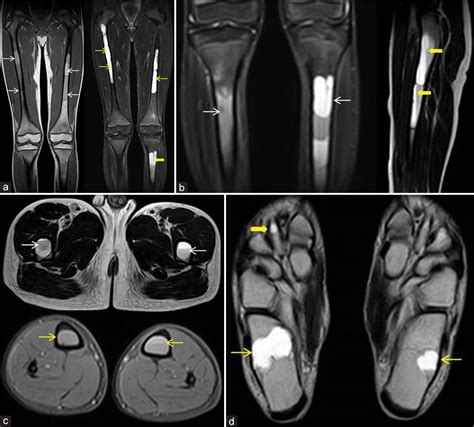

Diagnosis of a traumatic bone cyst typically involves a combination of clinical examination and radiographic imaging. Dental X-rays, such as periapical radiographs or panoramic radiographs, are commonly used to visualize the cyst. In some cases, a computed tomography (CT) scan or magnetic resonance imaging (MRI) may be recommended for a more detailed evaluation.

• Aneurysmal Bone Cyst: This is a benign, expansile lesion that can cause significant bone destruction and is more commonly found in the long bones.